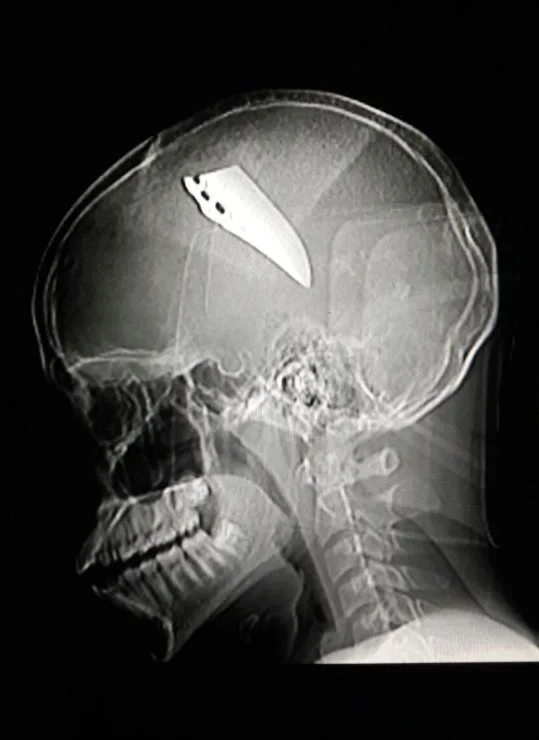

Once the crowd realized what had happened, a chorus of screams grew louder and more deafening as students and teachers watched in horror as David’s body became soaked with his own blood. He’d been brutally stabbed in his head with a butcher knife. The distal portion of the knife rammed through his skull with minimal resistance owing to the extreme sharpness of the blade. The shocking pain was immediate.

David pulled back and the knife broke, snapping into two and leaving seven centimeters of the distal portion embedded within his brain. The school went into shutdown and on-campus police officers took charge. David was transported to the hospital in critical condition but unlike my previous reports, this story isn’t told from the patient’s perspective but from the surgeon who operated on him that fateful afternoon.

It was a haunting reminder that this wasn’t just a patient, it was someone’s son, harmed while at an institution designed for no other reason than to provide him with a brighter future. Once X-rays were performed to assess the exact position of the blade, David was prepped and transported to the operating theater.

Sedated by general anesthesia, David’s head was shaved and was held in place with a three-point fixation device. The area was then cleansed and draped. Using a surgical blade, a skin incision was made and the underlying muscle and soft tissue were lifted off the skull and retracted. An oscillating bone saw was utilized and a bone flap was excised exposing the dura which covers the brain.

Fortunately, the knife didn’t damage the extensive network of nerves and blood vessels that traverse through the brain. The knife was gently removed and with great caution, water was flushed over the open brain and suctioned along with any possible broken metal fragments. The dura was closed with sutures and the bone flap was secured in position with titanium plates and screws. Finally, the muscle and skin were sutured close and the incision site was dressed with antibiotic ointment and sterile gauze.